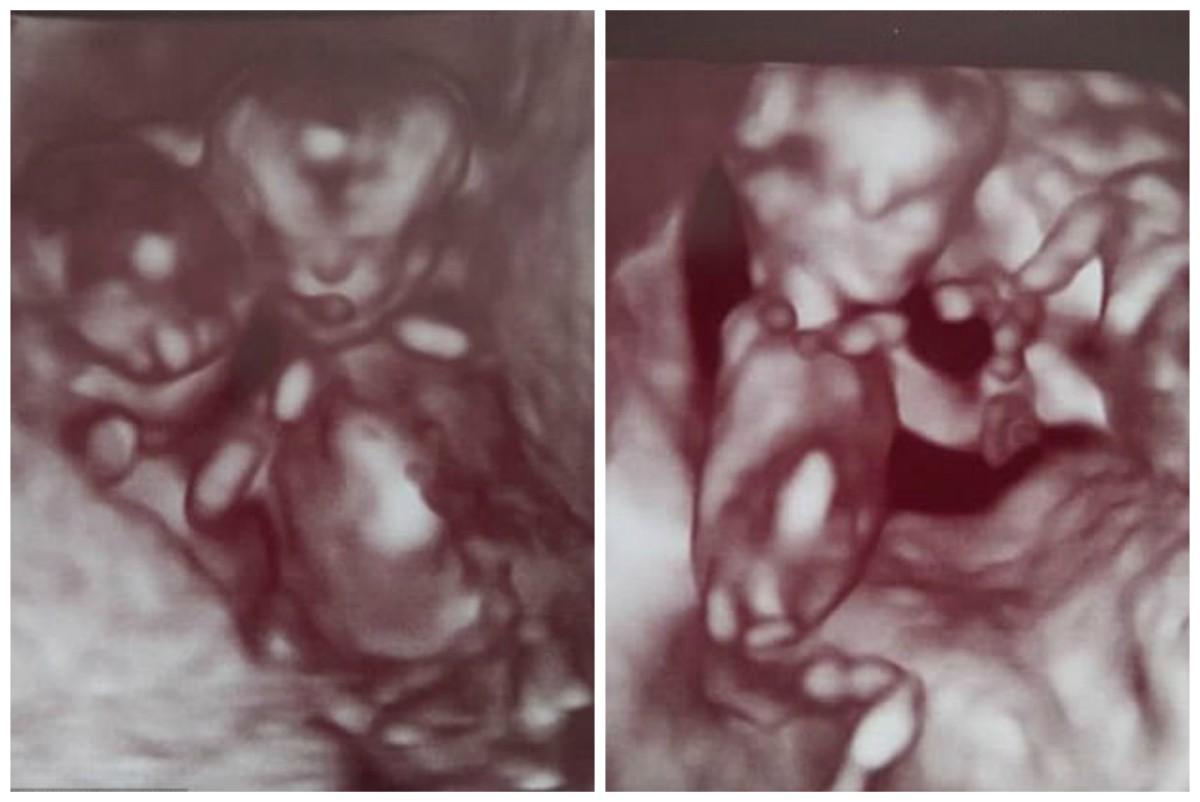

Αλλά τα πάντα άλλαξαν στο υπερηχογράφημα των 12 εβδομάδων, όταν οι γιατροί είπαν στη Vicky και τον Chris πως είδαν ότι τα δίδυμα είχαν μετακινηθεί σε μια στάση που τους έσωσε τη ζωή

“Προς έκπληξή μας, κατά το υπερηχογράφημα των 12 εβδομάδων, είδαμε ότι ήταν αγκαλιασμένοι μεταξύ τους και κρατούσαν ο ένας το χέρι του άλλου,” θυμάται η Vicky.

“Κρατούσαν ο ένας τον άλλον ζωντανό, παραμένοντας στάσιμοι, κι έτσι οι ομφάλιοι λώροι τους δεν μπερδεύτηκαν.”

Όμως, στο υπερηχογράφημα των 12 εβδομάδων, το ζευγάρι είδε κάτι μαγικό – τα αγόρια τους αγκαλιάζονταν και κρατούσαν ο ένας το χέρι του άλλου. «Με το να κάθονται σε αυτή τη στάση δεν μπερδεύονταν οι ομφάλιοι λώροι τους», είπε η Vicky.

“Ήταν ένα θαύμα.”